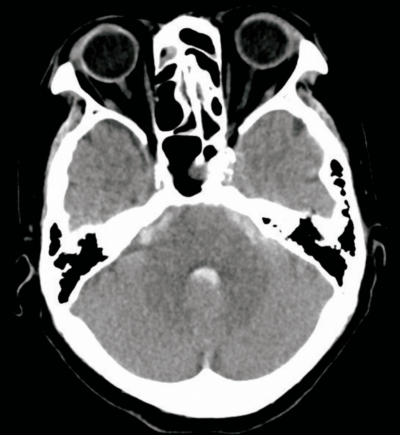

60歳の男性。突然起こった激しい後頭部痛、悪心および嘔吐を主訴に来院した。症状出現後、後頭部痛は少しやわらいだが、市販の鎮痛薬を服薬しても継続したため受診した。

来院時、意識は清明で項部硬直は認めなかった。頭部CTを別に示す。